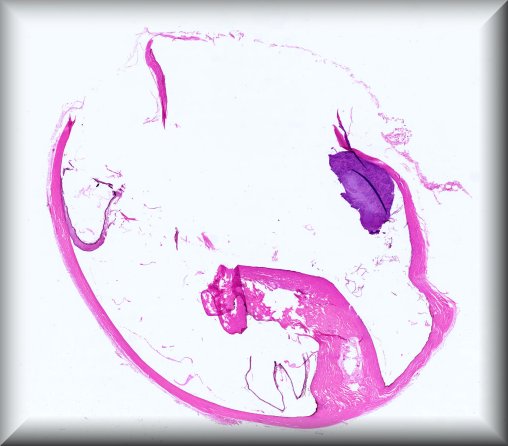

Julia Weller (Erlangen, Germany): Diffuse choroidal hemangioma, intraocular ossification, secondary angle closure glaucoma in a young female patient with Sturge-Weber syndrome. |